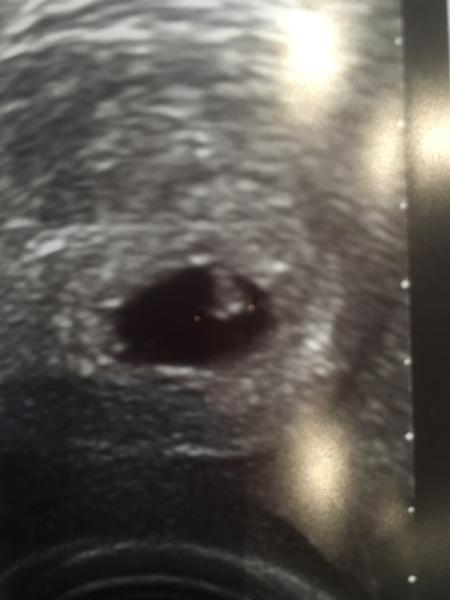

Hey Leute, passend kurz vorm Urlaub hat mir mein Gyn. heute das Herzchen meines Krümelchen gezeigt so ein tolles Gefühl

Danke 6+2 Wir gehen jetzt für 12 Tage in Urlaub, danach hab ich direkt wieder einen Termin und bekomme meinen Mutterpass